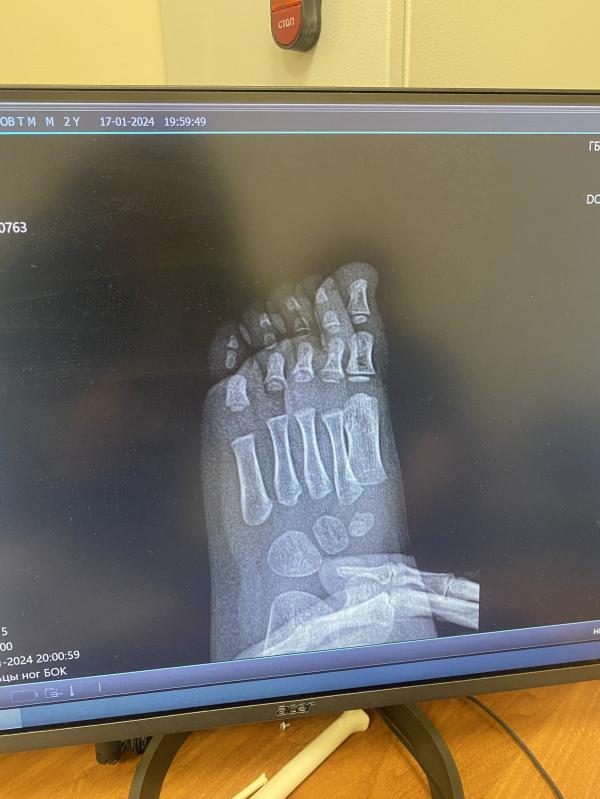

Есть ли тут кто разбирается в рентгене? У сына опух мизинец и красный весь, горячий. В травмпункте сказали ушиб. Я сомневаюсь((

Нет перелома.